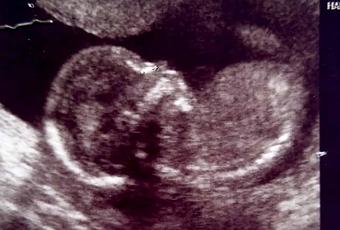

Ayer te fuiste formando y ya no solo te llevaba en mi sangre sino que ya tenías la forma como un grano de mostaza y luego de un fréjol con pequeños latidos que confortaban mi alma y mi corazón.